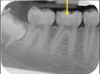

89

is the following periapical pathology or not?

yes - lamina dura tracking off